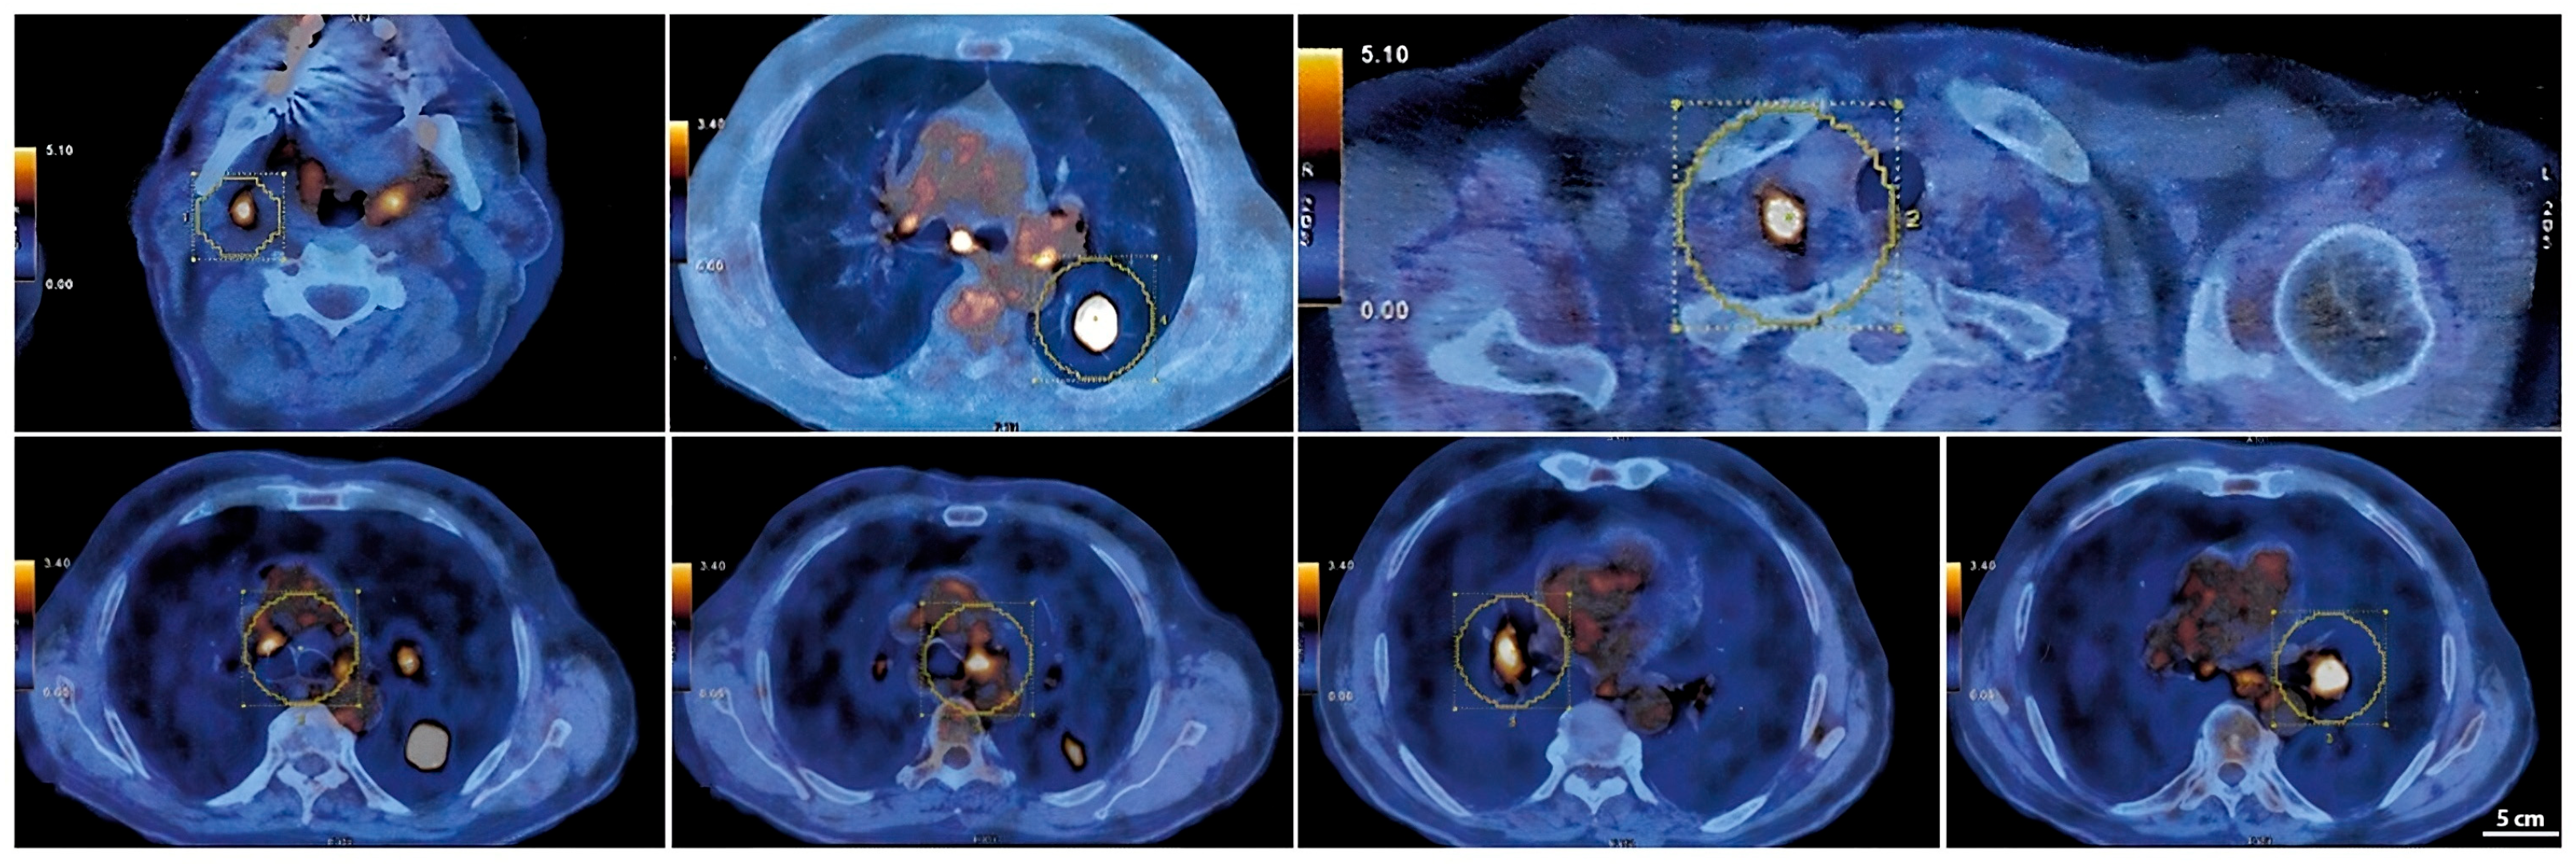

A PET-CT scan with 18F-FDG performed in March 2023 (Figure 3) revealed intense radiotracer uptake in the nodular lesion of the apical segment of the lower left lung lobe (SUV max 12.5). The scan also showed hypermetabolic lymph nodes in the Barety space (SUV max 4), aorto-pulmonary window (SUV max 5.1), subcarinal region (SUV max 6.4), and bilateral hilar regions (SUV max up to 6 on the left). Additional hypermetabolic lymph nodes were detected in the right supraclavicular region (SUV max 10.2) and in the ipsilateral lateral cervical region (SUV max 5.9), consistent with advanced-stage disease (T2aN3M0) [7].

Figure 3.

PET-CT images of hypermetabolic lymph nodes and the left lower lobe pulmonary lesion.